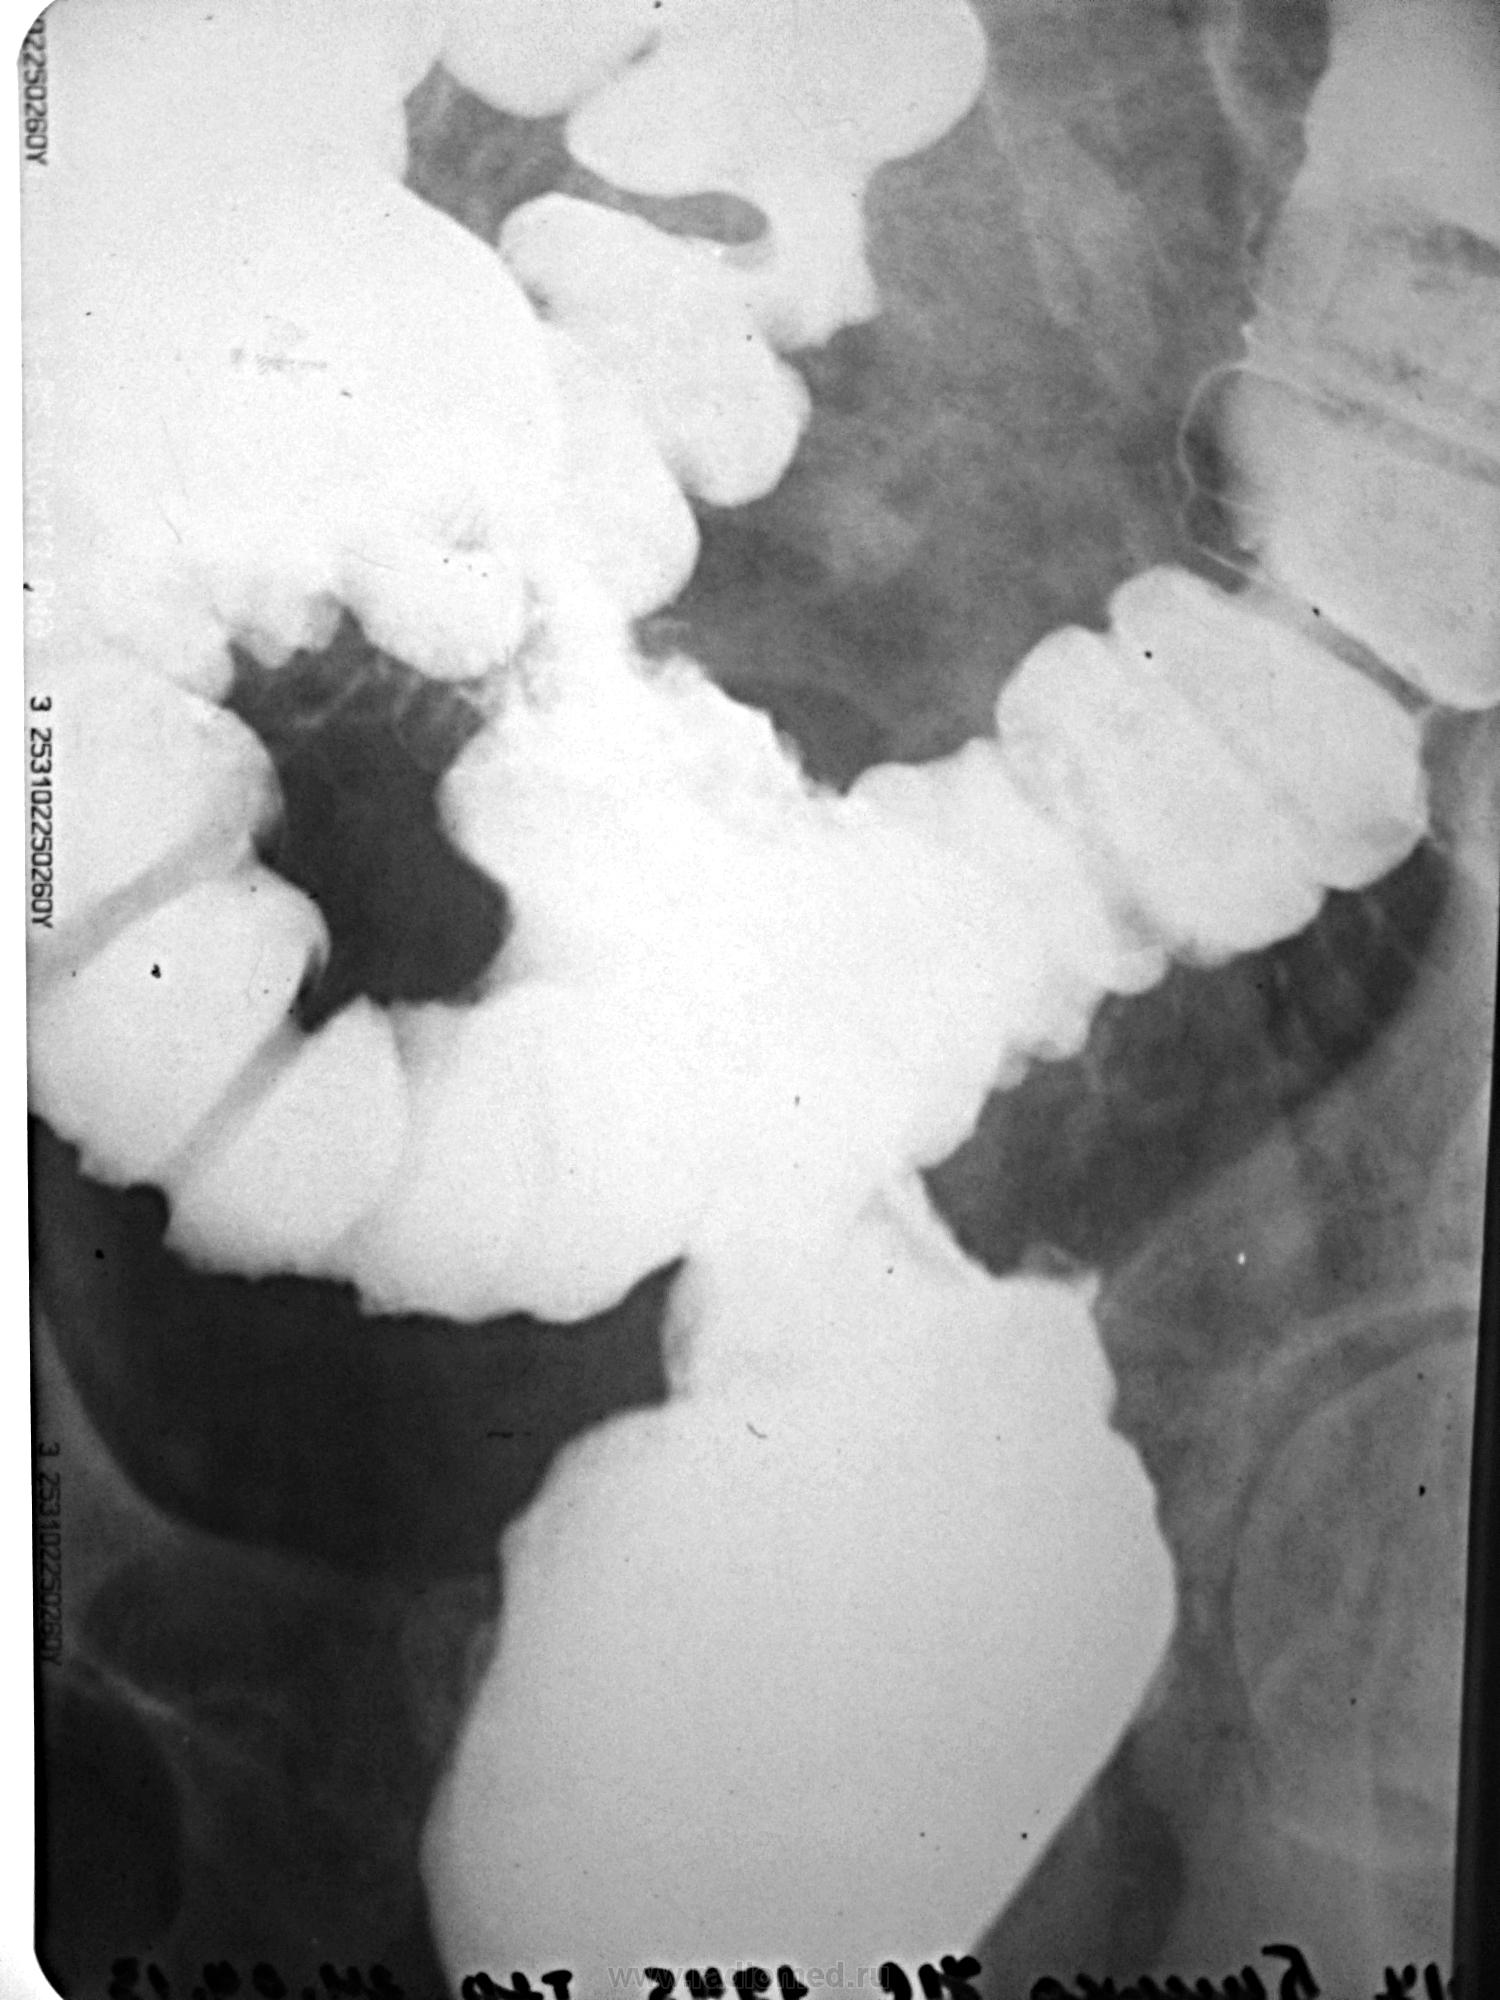

Пациент с жалобами на запоры. Ирригоскопия после RRS (тубус после 10 см не прошел).

Коллега, а обзорный снимок не делали и что написали по status loclis на RRS? Какое-то органическое поражение дистальных отделов толстой кишки с массивной циркулярной инфильтрацией и боковыми затёками  контраста ( рак ? болезнь Крона? неспецифический язвенный колит?)

Извините за молчание (уезжал). На RRS - циркулярная бугристая опухоль грязно-серого цвета. На гистологии - аденокарцинома. Насчет обзорного снимка - зачем? - выложены прицельные РГ.